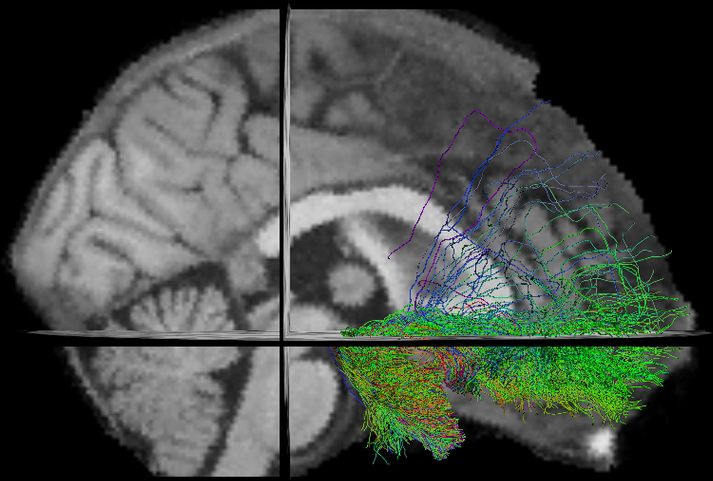

- TractFiltering (Cousineau et al 2016. ISMRM, Coté et al 2015. ISMRM)

- Tractometry (Cousineau et al 2016. ISMRM)

FA

NUFO

Metrics

- Mean value per bundle

- Mean value per point

- Profile

- Volume